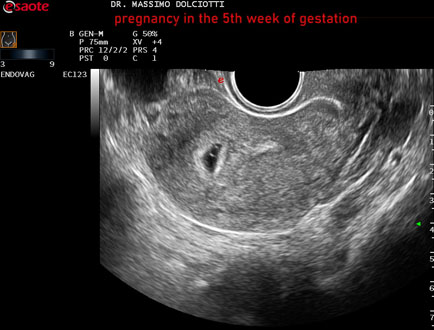

Data inserimento: 12/12/2025

Ecografia del: 31/11/2025

Strumento: Esaote MyLab Eight

Sonda: Convex Multifrequenza 1-8 MHz ed Endocavitaria Multifrequenza 3-9 MHz

Età Paziente: F 28 anni

Motivazione dell'esame: amenorrea e BETAHCG POSITIVO 17 mila.

Commento all'esame: le immagini ed il video documentano la camera gestazionale delle dimensioni di 13 x 7 mm e presenza di sacco vitellino delle dimensioni di 3,3 mm.

Conclusioni: gravidanza alla quinta settimana di gestazione (pregnancy in the 5th week of gestation).

Presentazione: Dr. Massimo Dolciotti - Ancona

Elaborazione digitale: Andrea Dini - Ancona